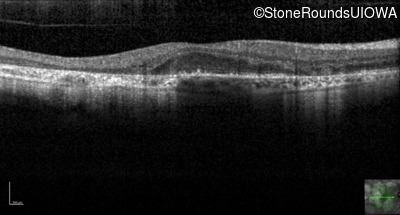

Age at visit: 51 years

This 51 year old woman first experienced some abnormality in her distance vision when she was 27 years old. She feels that her vision has been stable since that time.